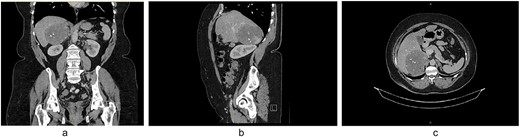

A 61-year-old obese (BMI = 35.2) female of Maltese background attended her general practitioner with non-specific intermittent abdominal pain over 5 years. Her past medical history included hypertension and hypercholesterolaemia, and previous surgical history of hysterectomy and laparoscopic appendicectomy. She did not have any signs or symptoms suggestive of a functional adrenal mass. She denied significantly elevated blood pressure, flushing, syncope or palpitations. Clinically, she had no abdominal masses or regional tenderness on deep palpation. A CT scan demonstrated a right-sided adrenal lesion (9.5 × 8.6 cm) with fat lobules, calcification and heterogeneous progressive enhancement (Fig. 1).

(a) CT coronal, (b) CT sagittal, (c) CT axial scans demonstrating a right-sided adrenal lesion (9.5 × 8.6 cm) with fat lobules, calcification and heterogeneous progressive enhancement.